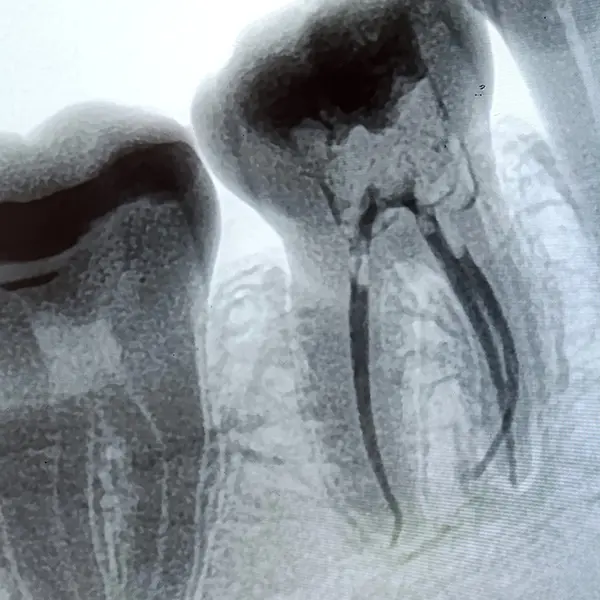

Контроль: рентгеновские снимки